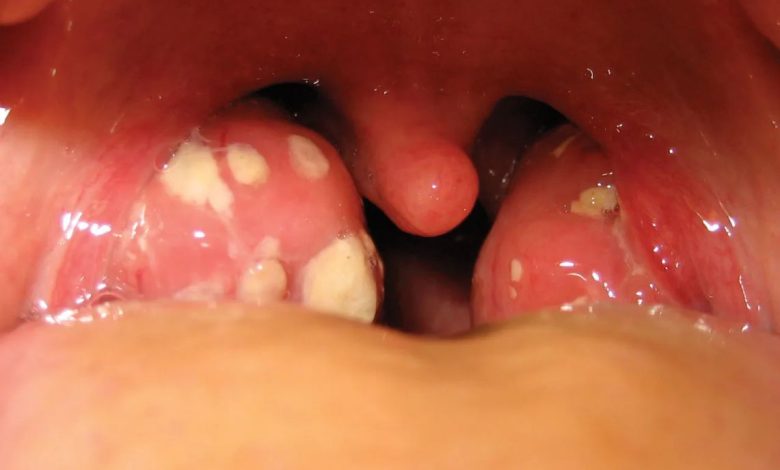

تورم لوزهها

پزشکان معمولاً مونو را بر اساس علائم و معاینه فیزیکی، همراه با آزمایش خون تشخیص میدهند. تشخیص ممکن است شامل موارد زیر باشد:معاینه فیزیکی. پزشک ممکن است تورم غدد لنفاوی، لوزهها، کبد یا طحال را بررسی کند.آزمایش خون. این آزمایشها ممکن است شامل موارد زیر باشد:آزمایش آنتیبادی هتروفیل، که اغلب آزمایش مونواسپات نامیده میشودآزمایشهایی برای آنتیبادیهای ویروس اپشتین بار.شمارش کامل خون که گلبولهای سفید غیرطبیعی را نشان میدهد.طبق گفته مراکز کنترل و پیشگیری از بیماریهای ایالات متحده (CDC)، آزمایش اولیه ممکن است منفی باشد، بنابراین گاهی اوقات اگر علائم به شدت نشان دهنده مونو باشد، آزمایش مجدد لازم است.

بیشتر افراد به طور کامل بهبود مییابند، اما مونو ممکن است در طول بهبودی نیاز به صبر داشته باشد.عوارض کوتاه مدت ممکن است شامل تورم شدید گلو، کم آبی بدن و عفونتهای ثانویه مانند گلودرد استرپتوکوکی باشد.عوارض نادر اما جدی ممکن است شامل پارگی طحال، التهاب کبد، کاهش تعداد گلبولهای خون و درگیری قلب یا سیستم عصبی باشد، طبق گفته کلینیک مایو و NIH. این موارد غیرمعمول هستند اما نیاز به مراقبت پزشکی فوری دارند.